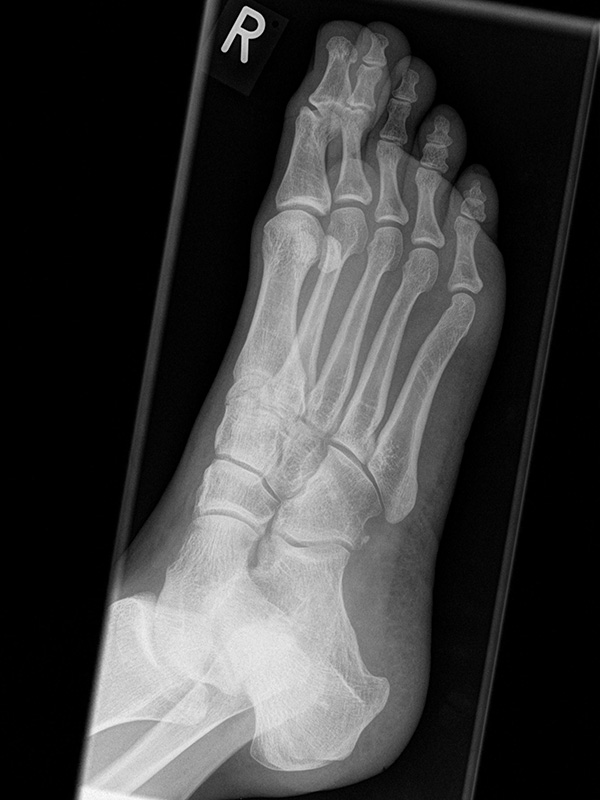

Fuß dorsoplantar (dp) ohne Belastung

Positionierung:

• Patient liegt auf dem Rücken, der Fuß wird auf die Röntgenkassette aufgestellt, das Knie gebeugt.

• Der Zentralstrahl wird auf das Tarsometatarsalgelenk II zentriert.

• Die Röntgenröhre ist 15° vertikal gekippt.

• Anm: Auch wenn der Fuß nicht belastet wird, sollte er auf die Röntgenkassette aufgestellt werden. Aufnahmen des hängenden Fußes sind nur eingeschränkt beurteilbar.

Kennzeichen des Röntgenbildes:

• Die Kippung der Röhre um 15° erlaubt eine bessere Beurteilung der Fußwurzelgelenke.

• Darstellung der Knochen.

• Winkelmaße (z.B. Intermetatarsalwinkel) beziehen sich auf belastete Aufnahmen. Es besteht eine erhebliche Differenz zwischen unbelasteten und belasteten Aufnahmen.

Besondere Bemerkungen zum Beispielbild:

• Der Patient erlitt ein Mittelfußtrauma. Unter Frakturverdacht erfolgten die unbelasteten Aufnahmen.

• Die Frakturlinie im Os cuneiforme I ist in der dp nicht zuverlässig erkennbar.

• Unauffällige Abbildung des restlichen Fußskeletts.

• Für die OP-Planung erfolgte dann noch ein Schnittbildverfahren.

Zur Vollansicht und zum Lesen der Bildbeschreibung bitte die Bilder anklicken.